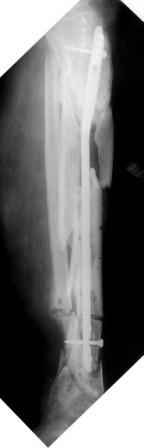

Коллеги!Позвольте продолжить обсуждение темы «ложный сустав левой голени.» Больной К 45 лет, начало см. http://www.weborto.net/forum/1228422607/ И рассказать о результатах проделанной работы. Остановились на следующей тактике 1) Наложить Аппарат Илизарова. В аппарате восстановить оси трех смещенных относительно друг-друга фрагментов большеберцовой кости. Устранить вальгусную деформацию дистального отдела большеберцовой кости. Что и было выполнено. - Была выполнена репозиция в аппарате (рис1) 2) После репозиции более очевидна стала проблема дефекта кости в верхней трети голени, два фрагмента свободно лежат. Остановились на варианте перехода на интрамедуллярный синтез стержнем с покрытием костный цемент+ванкомимцин и замещении дефекта с помощью транспорта фрагмента (рис 2) 3) Третьим этапом наложили модуль на промежуточный фрагмент.(рис 3) И начали его транспорт на стержне в проксимальном направлении. (рис 3 а) Надеемся что «вырастет» регенерат в дистальном отделе, а в проксимальном отделе фрагмент «упрется» и прирастет. Хочу сказать слова благодарности за обсуждение на форуме этого случая. Особые слова благодарности Иванову Павлу Анатольевичу!!! Он помогал Словом, а самое главное делом. Приезжал, оперировал! За что ему нижайший поклон! С ув Коробушкин Г

Меня расстраивает значительное вальгусное смещение проксимального отломка большеберцовой кости. Оно очень значительное. Рассверливание

костно-мозгового канала во время операции было непростым, и за время его проведения канал в проксимальном отломке образовался избыточным по

диаметру. Это в определенной мере способствовало образованию данного смещения. Жаль, что в конце операции мы недооценили его степень, иначе

бы устранили его при помощи винта-поллера. Может быть, участники Ортофорума что-либо посоветуют по этому поводу. Стоит ли как-то попытаться исправить ситуацию?

Да, это единственное, что "царапает глаз" при разглядывании этой интересной серии снимков.

Для восстановления оси "по-правильному" надо извлечь гвоздь, ввести отклоняющий винт или спицу, и ввести гвоздь повторно. А пытаться

исправить ось с гвоздем внутри мэтрами, например, проф. Шнеттлером, не рекомендуется. Мы, однако, попробовали - получается. Надо убрать запирающие винты из центрального отломка. В данном случае, при наличии не перелома, а дистракционного диастаза, надо использовать дистрактор. С помощью спиц которого, введенных с гиперкоррекцией, ось и исправить. Раз канал там широкий, получиться должно легко. После чего ввести винт кнаружи от гвоздя, а потом и винты через гвоздь.